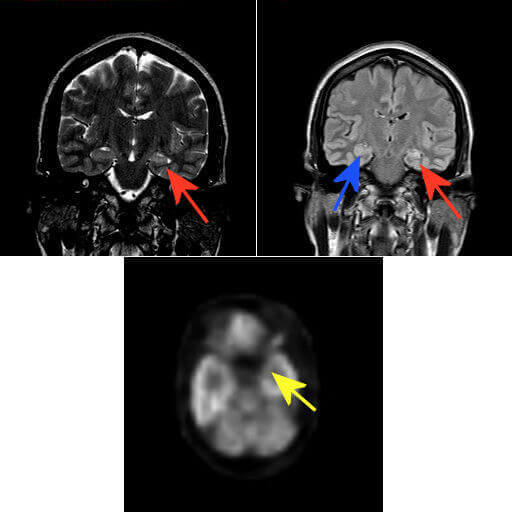

Figure 1: A. Coronal T2 weighted, B. Coronal FLAIR. Arrows point to the mesial temporal lobes. Blue arrow points to the right hippocampal formation which is normal in size and signal intensity. Red arrow points to the left hippocampus which is smaller and more T2/FLAIR signal hyperintense relative to the right. C. Axial PDG-PET. Yellow arrow points to relative hypometabolism of the cortex in the left mesial temporal lobe relative to the right.

MRI is the neuroimaging modality of choice in MTS. The affected hippocampus demonstrates volume loss and increased T2/FLAIR signal corresponding to gliosis. Fluorodeoxyglucose position emission tomography (FDG –PET) is also helpful in the diagnosis, demonstrating decreased radiotracer uptake in the mesial temporal lobe due to the loss of metabolically active cortical neurons.